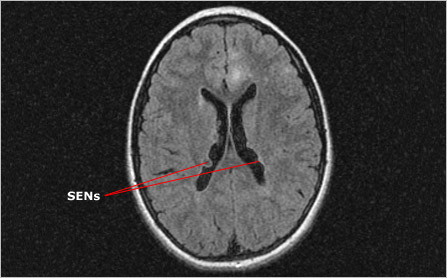

MRI showing SENs

Axial brain MRI showing subependymal nodules (SENs)

Like cortical tubers, subependymal nodules (SENs) are seen in approximately 80 percent of people with TSC. Typically these benign tumors arise along the ependymal lining (walls) of the lateral ventricles, the spaces that contain cerebrospinal fluid. They vary greatly in size and number, ranging from 2-10 mm in diameter and usually numbering more than one.

And like cortical tubers, SENs form early in brain development and are made up of highly disorganized and dysfunctional cells. However, while tubers have cells with both neuronal and glial characteristics, SENs are composed only of glial cells. SENs also differ from the relatively static tubers in that their growth can outpace that of the surrounding tissue, causing them to protrude into the cavities of the ventricles. While only 15 percent of SENs grow larger than 1 cm in diameter, those that do become classified as SEGAs and are cause for concern.